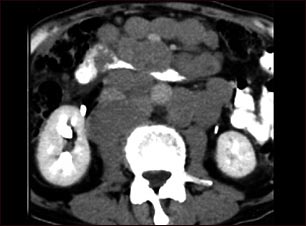

Linfoma maligno - TC

Esta TC abdominal muestra masas tumorales (linfomas malignos) en el área posterior a la cavidad peritoneal (espacio retroperitoneal).